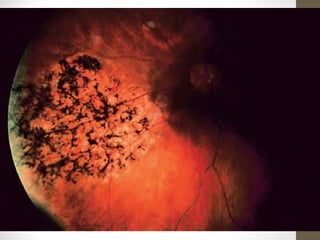

• Triad of

• bone-spicule retinal pigmentation

• arteriolar attenuation

• ‘waxy’ disc pallor

Progression

• Bilateral mid-peripheral intraretinal perivascular

‘bone-spicule’ pigmentary changes with

arteriolar narrowing

• Then a gradual increase in density of the

pigment

• Anterior and posterior spread

• Peripheral pigmentation may become severe,

with marked arteriolar narrowing and disc pallor

• The macula may show

• Atrophy

• epiretinal membrane formation

• cystoid macular oedema (CMO)

• Myopia is common.

• Optic disc drusen occur more frequently